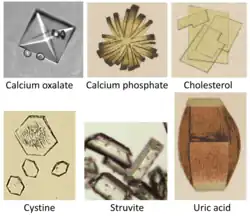

Calcium phosphate stones account for approximately 15% of kidney stone disease. Calcium phosphate stones tend to grow in alkaline urine, especially when Proteus bacteria are present. It is the most common type in pregnant women.[7]

Urine crystals comparison, with calcium phosphate crystal depicted at top center.

Urine crystals comparison, with calcium phosphate crystal depicted at top center. -